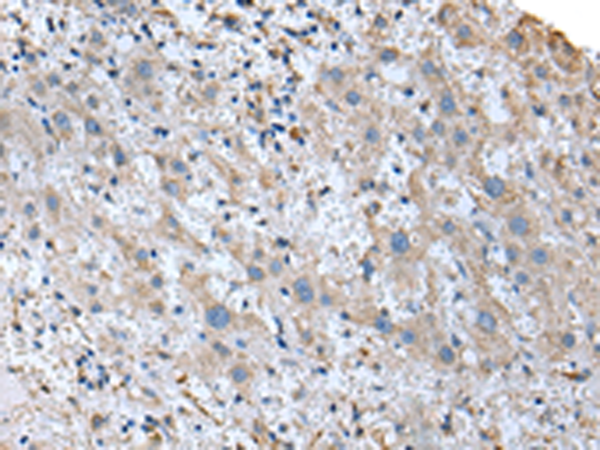

分类: 科研抗体货号: P09110别名: RCDG1应用: IHC反应种属: Human